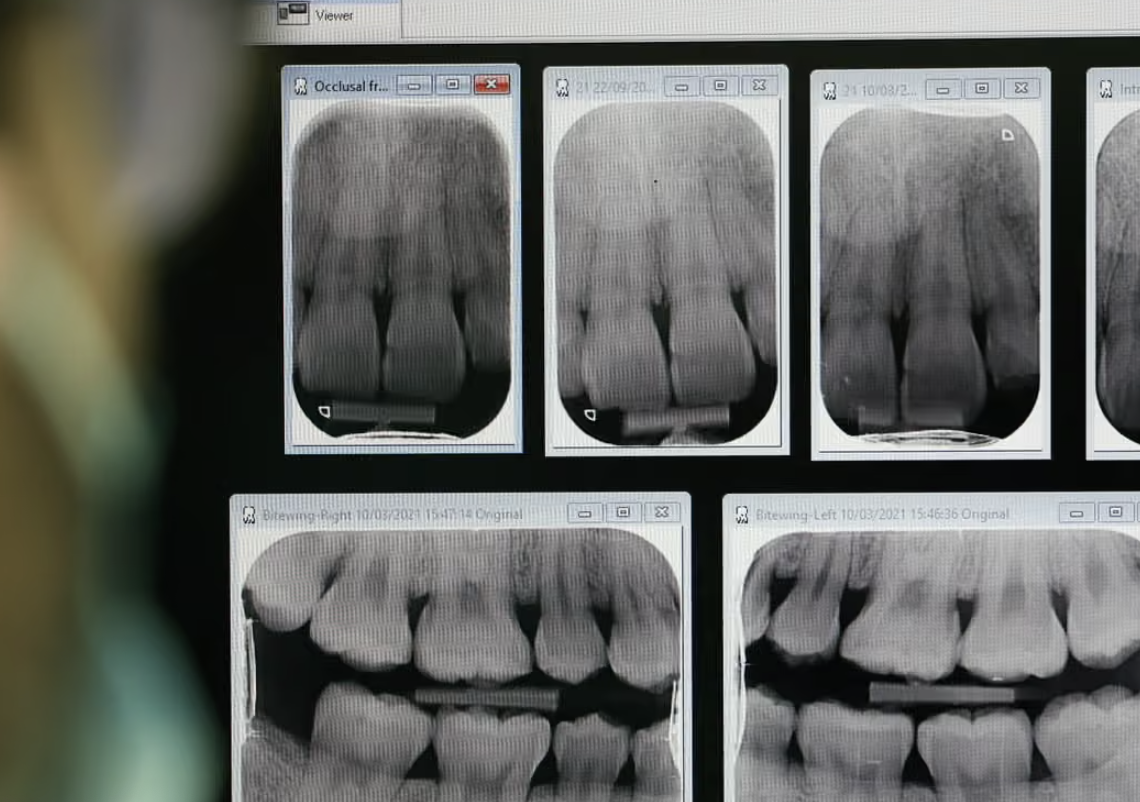

أعلنت الحكومة البريطانية عن خطة جديدة لزيادة حوافز أطباء الأسنان في إنجلترا، بهدف تسهيل حصول المرضى على مواعيد الطوارئ ضمن نظام الرعاية الصحية الوطنية (NHS)، في خطوة تهدف لمعالجة النقص الحاد في خدمات الأسنان، وسط تحفظ خبراء حول تأثيرها الفعلي على جودة الرعاية.

وحسب ما ذكرته صحيفة الغارديان “The Guardian” يعاني ملايين الأشخاص في إنجلترا من صعوبة الوصول إلى خدمات الأسنان، ما أدى إلى ما وصفه البعض بـ"صحارى الأسنان" وحتى ممارسات "الأسنان الذاتية". وأشار تقرير لمراقب المرضى نشر الاثنين إلى أن بعض الأشخاص لم يحصلوا على رعاية عاجلة رغم وجود توجيهات NHS، مما دفع البعض لخلع أسنانهم بأنفسهم.

وأظهرت أحدث نتائج مسح صحة الفم لدى البالغين أن 41% من الأشخاص لديهم علامات واضحة لتسوس الأسنان، وهو معدل مشابه لمستويات أواخر التسعينيات.